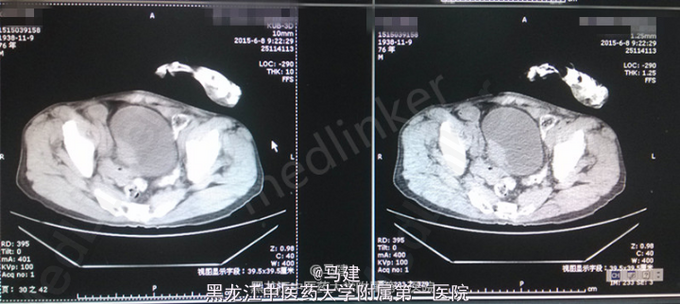

查体:T:36.2℃,P:64次/分,R:20次/分(规则),BP:138/83mmHg。神志清,精神可,全身浅表淋巴结无肿大,心肺腹未及明显异常,脊柱四肢活动自如。 专科情况:双肾区无明显压痛及叩击痛,输尿管行走区域正常,无压痛,膀胱叩诊呈浊音,无压痛,阴茎发育正常,无包茎或包皮过长,尿道外口正常,无狭窄、炎症分泌物,双侧阴囊对称,睾丸及附睾正常。前列腺直肠指检呈I°增大,中央沟存在,质地正常,无触痛,无结节。 入院后检查:血常规:RBC 4.29*10^12/L,Hb 123.0g/L,HCT 37.7%,WBC 3.55*10^9/L;尿常规:红细胞(+),红细胞计数 101.0/μl;尿培养:无细菌生长;三次尿脱落细胞学检查中一次偶见可疑Ca细胞;泌尿系CT示膀胱右侧壁见大小约23*42mm的软组织密度影。